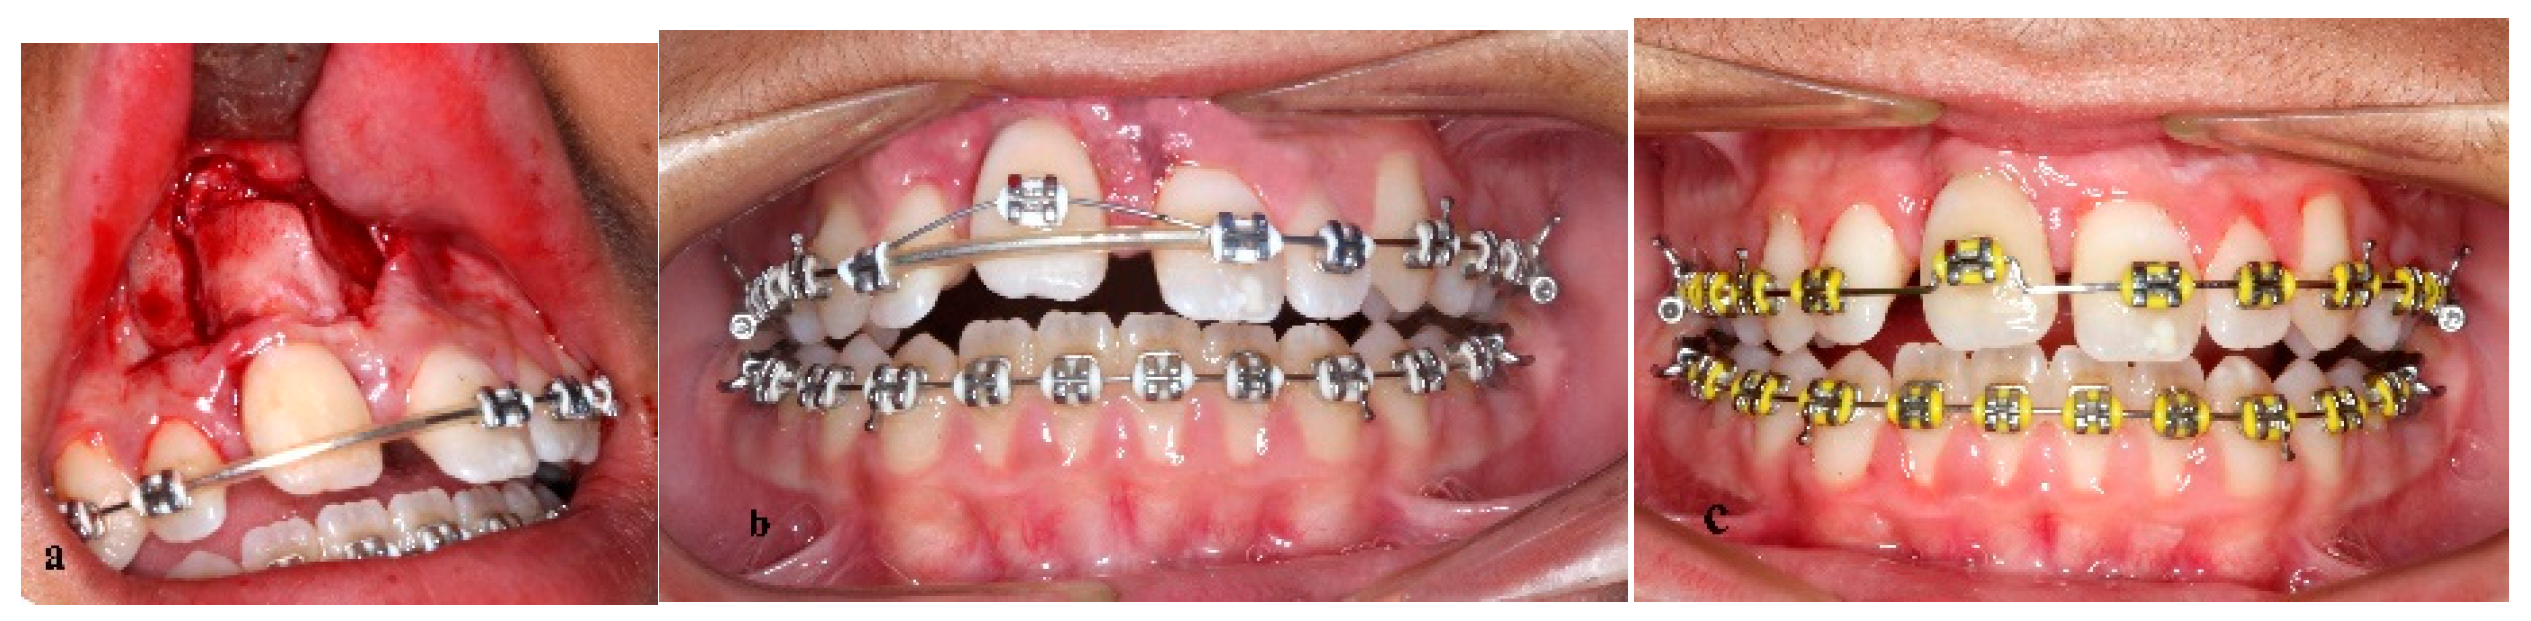

Treatment of an Avulsed and Ankylosed Incisor through Single Tooth Alveolar Osteotomy and Conventional Orthodontic Mechanisms

2. Materials and Methods

3. Results